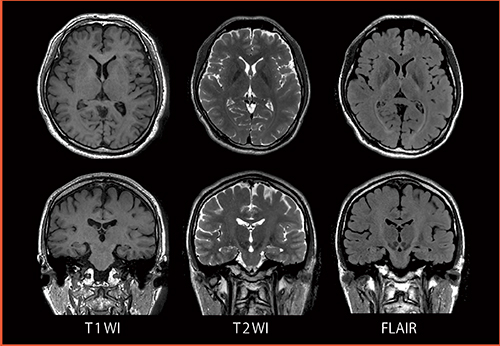

図4 3D FSE(isoFSE):Sagittal Acquisition Reformat Images

T1WI, T2WI,FLAIRをサジタルで撮像し,その後アキシャル画像,コロナル画像に再構成した。効率良く短時間で撮像し,撮像後に他の断面を再構成することで検査スループットの向上が見込める。